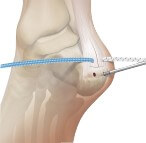

La technique endoscopique

Le chirurgien réalise deux mini-incisions de 5 mm. À l’aide d’une caméra et de petits instruments, il peut :

- Nettoyer le tendon et retirer les tissus inflammatoires,

- Enlever le tendon accessoire appelé plantaire grêle (qui, par sa cinétique différente, peut frotter sur le tendon d’Achille et entretenir l’inflammation),

- Réaliser un « peignage » : de fines incisions dans les fibres du tendon, qui déclenchent un processus naturel de cicatrisation.